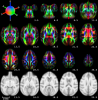

DTI-TEMPLATE-RHESUS-MACAQUES

DTI-TEMPLATE-RHESUS-MACAQUES Images

3 Images available.